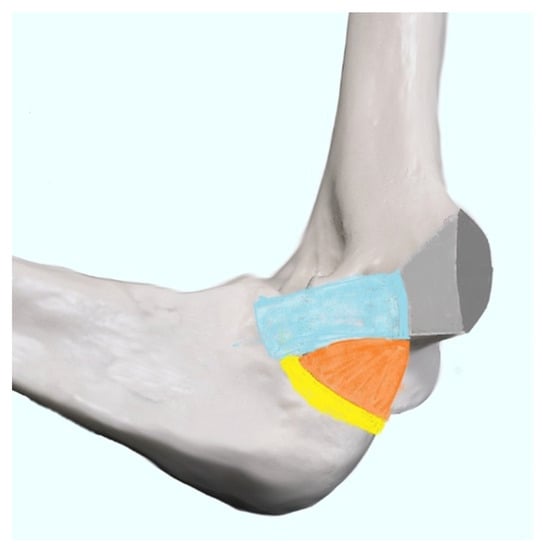

The Technique of Ultrasound Examination of the Medial Portion of the Elbow

4.4. Ulnar Collateral Ligament Injury